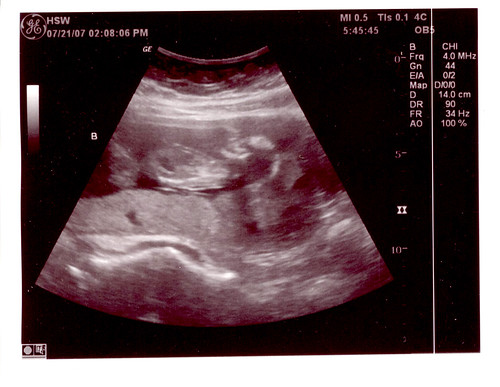

Oh, pics? Want to see them? C was being uncooperative, so we only have A & B. But like it matters – they basically look all the same anyway. 😛